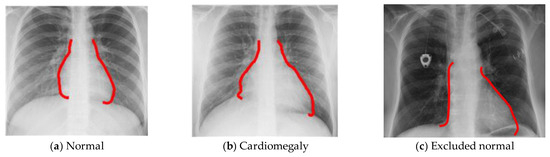

3.1. Preprocessing Data